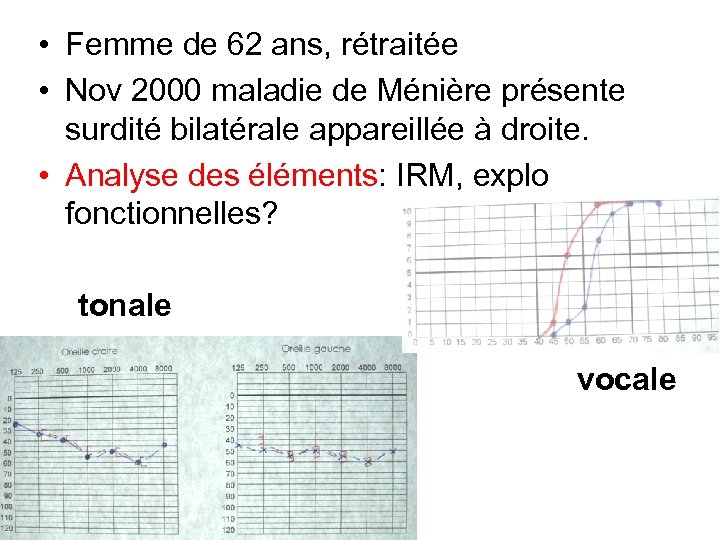

• Femme de 62 ans, rétraitée • Nov 2000 maladie de Ménière présente surdité bilatérale appareillée à droite. • Analyse des éléments: IRM, explo fonctionnelles? tonale vocale

• Femme de 62 ans, rétraitée • Nov 2000 maladie de Ménière présente surdité bilatérale appareillée à droite. • Analyse des éléments: IRM, explo fonctionnelles? tonale vocale